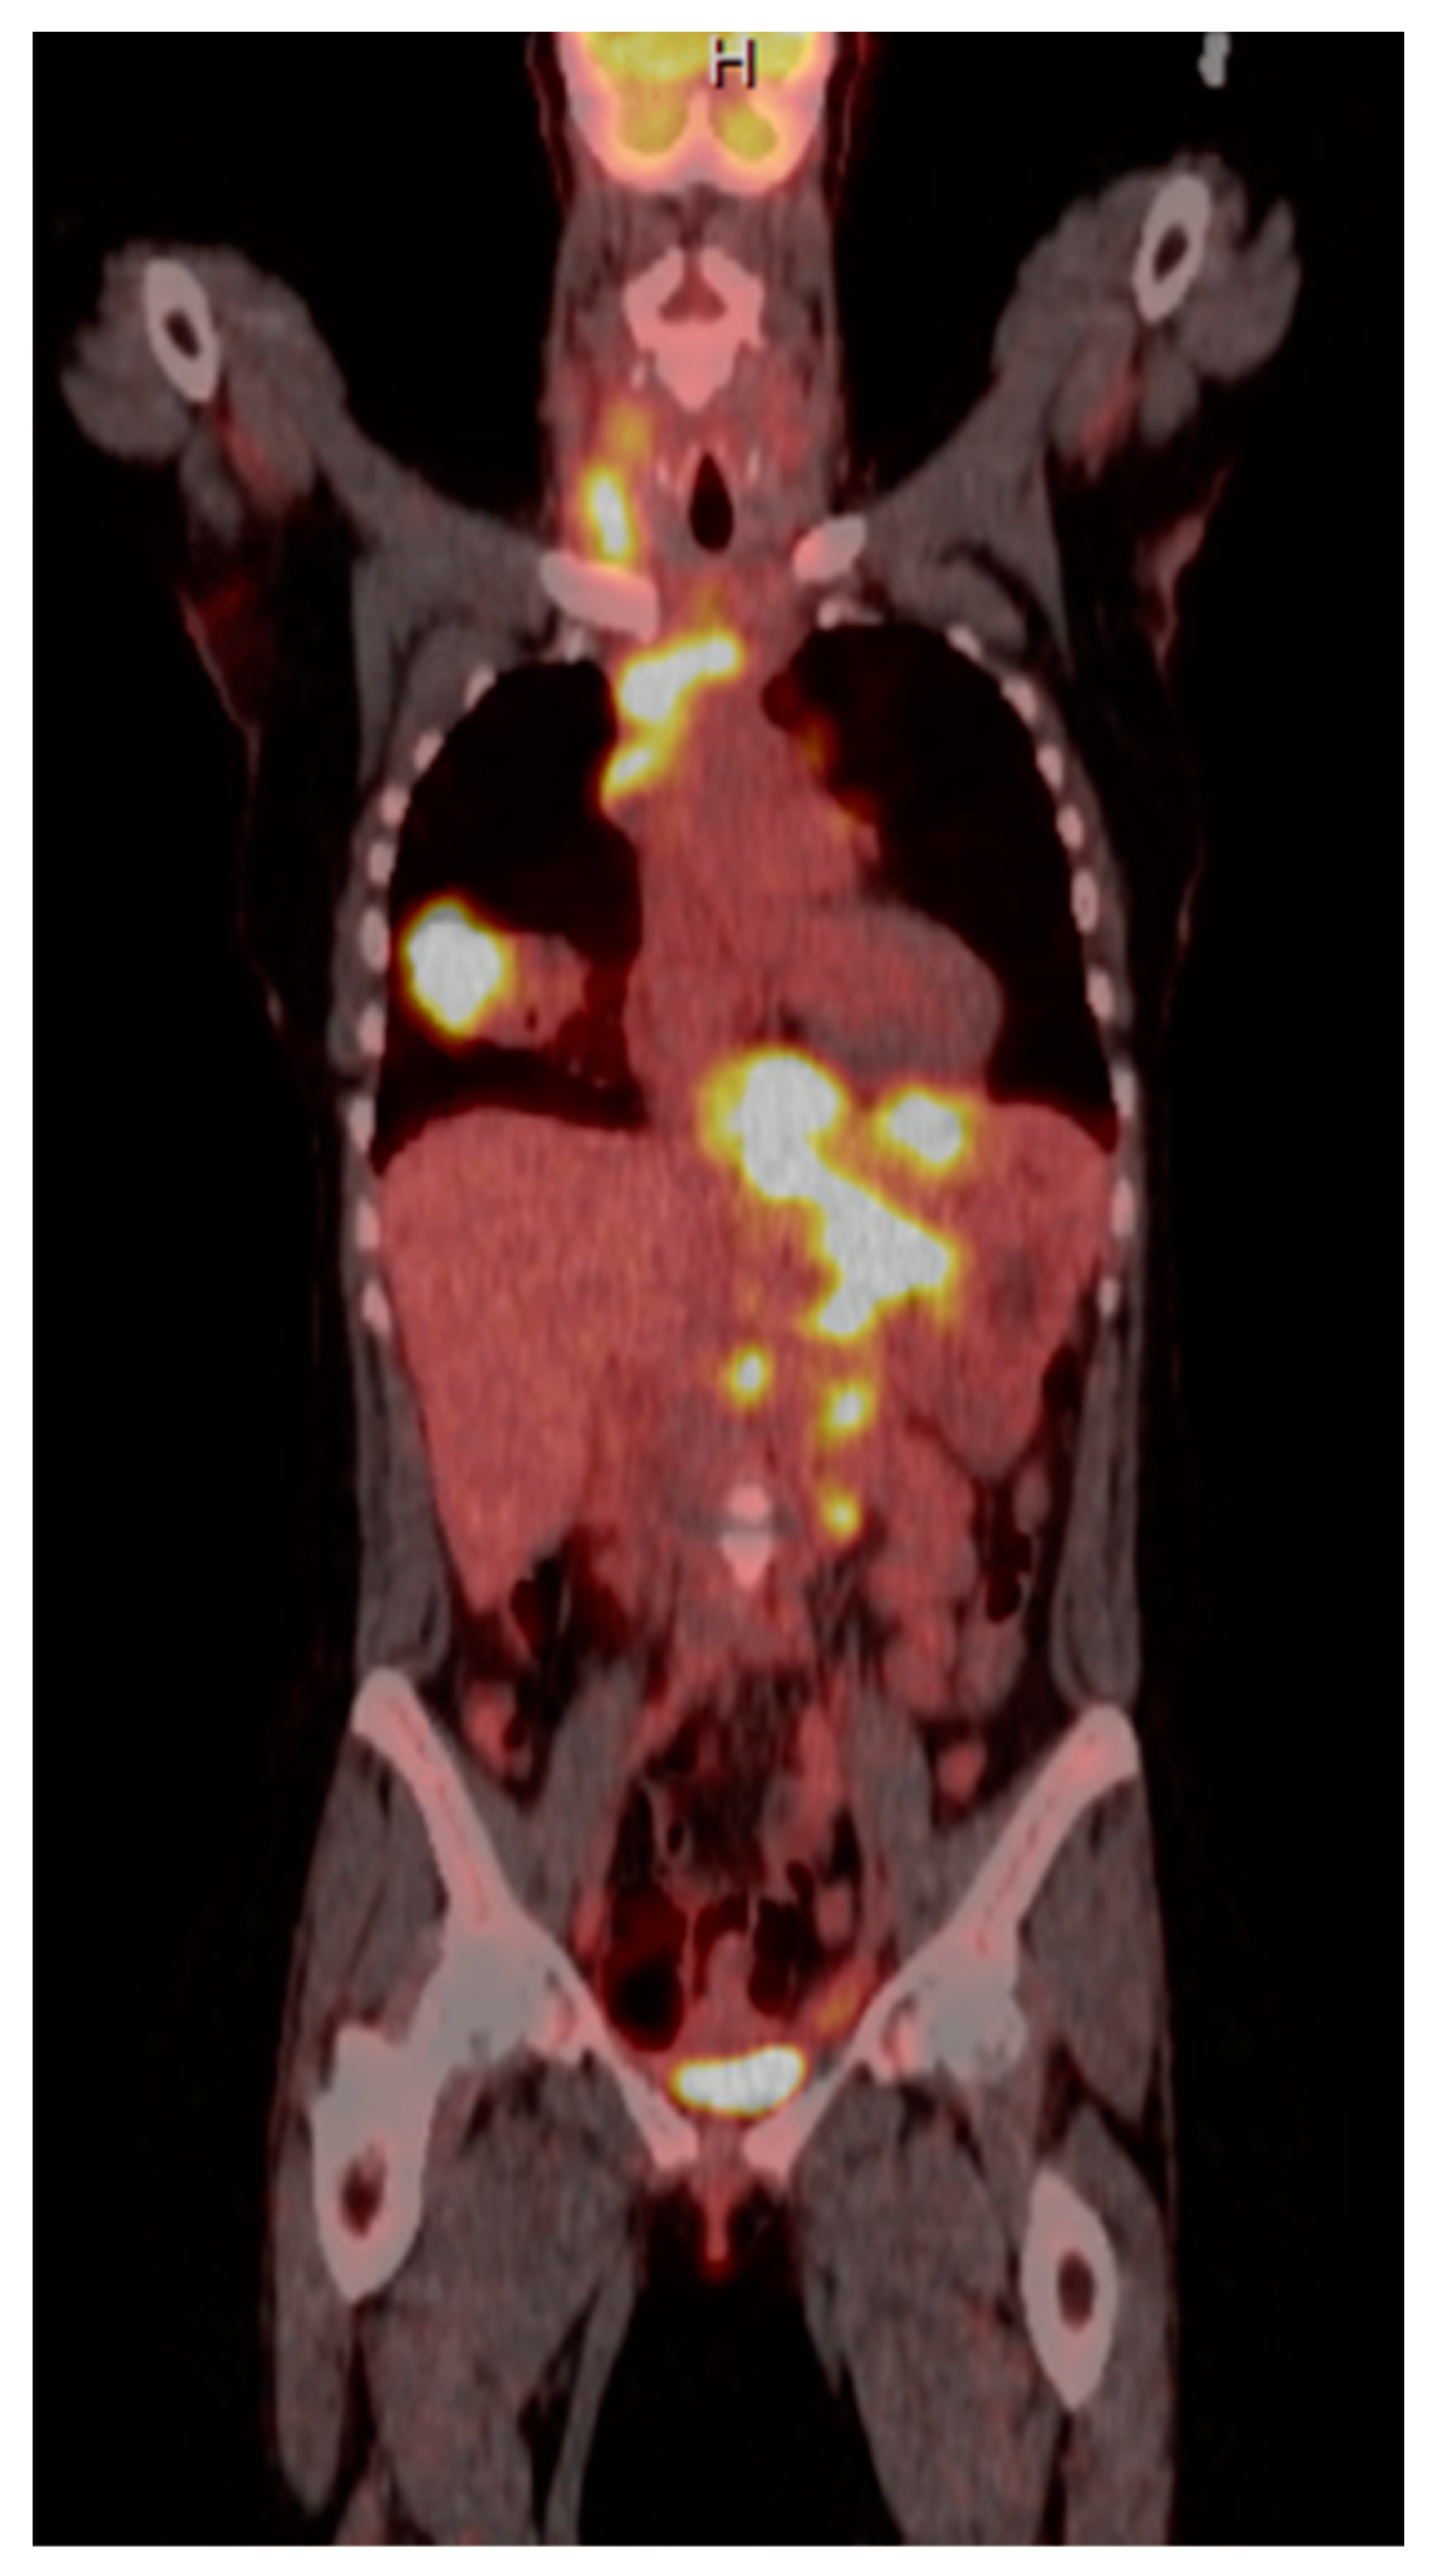

| 1 | F | 66 | Skin | Fundus, cardia, and body | Polypoid lesions with superficial ulcers | Esophagus, duodenum, mediastinum, cervical soft tissue, pancreas | Metastatic malignant melanoma | Radiotherapy and immunotherapy | Comfort care and death 5 days after EGD diagnosis of metastasis |

| 4 | F | 73 | Kidney | Fundus and body | Multiple large friable masses | Liver and lungs | Clear cell renal carcinoma | Nephrectomy, chemotherapy, immunotherapy (Axitinib) | Death 10 days after EGD diagnosis of metastasis |